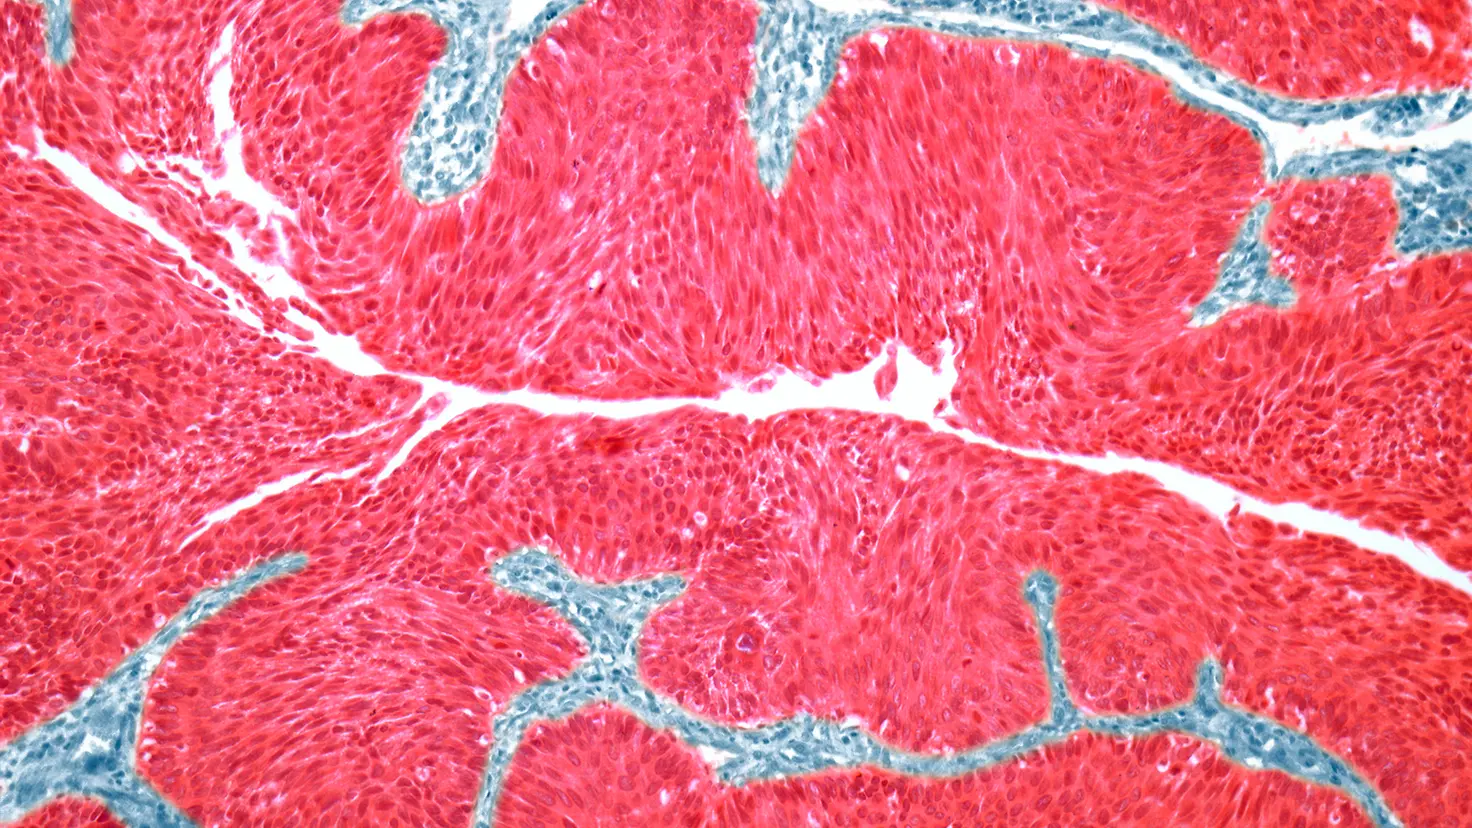

Ein Harnblasenkarzinom ist ein bösartiger Tumor. Er entsteht meist in der Blasenschleimhaut, der innersten Schicht der Blase. Wenn die Erkrankung nicht entdeckt wird, kann das Karzinom auch in tiefere Schichten der Blase vordringen und sich über die Blase hinweg auch in benachbartes Gewebe ausbreiten.

Stilisierte Darstellung einer Blasenkrebszelle